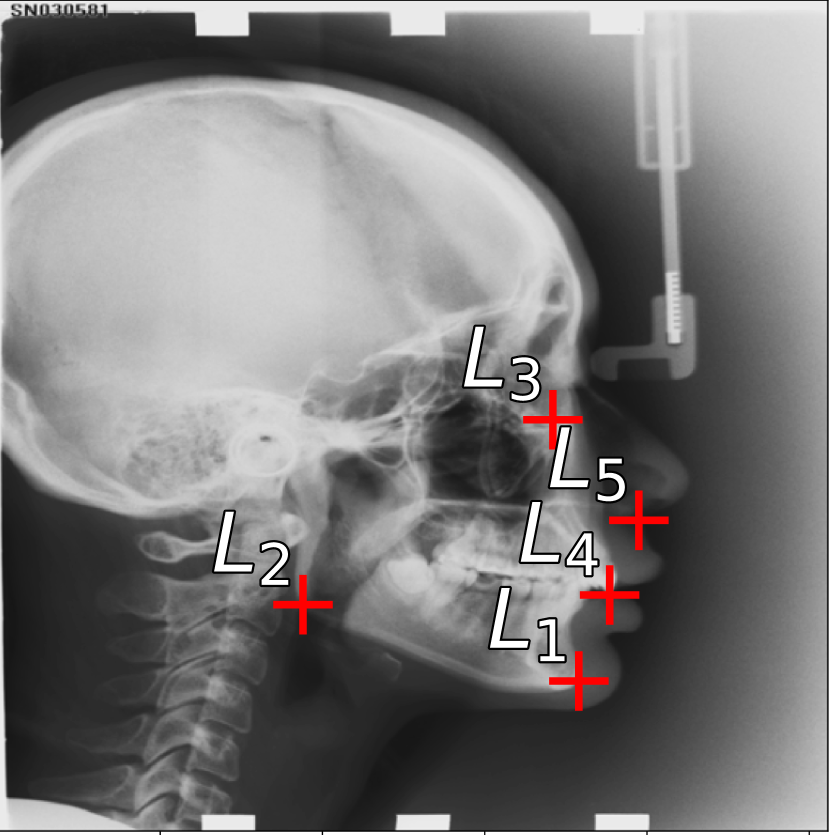

Figure 2: (a) Landmarks for Short Axis (SA) CMR: Magenta = superior right ventricle insertion point valve; Yellow = inferior right ventricle insertion point; Red = inferior lateral reflection of right ventricle free wall. (b) Landmarks for 4 chamber (4CH) CMR: Magenta = tricuspid valve; Yellow = mitral valve; Red = apex of left ventricle. (c) Subset of Landmarks included in the Cephalometric dataset [8]. Displayed landmarks are used in the aleatoric uncertainty analysis (Sec. 6.7).

To test generalizablity across imaging modalities, we use a third dataset consisting of Cephalometric Radiographs, in which the images contain repetitive structures [8]. The dataset has a total of 19 annotated landmarks, where we use the junior annotator as the ground truth (following the convention of [34, 12, 10]). For our study of aleatoric uncertainty in Sec. 6.7, we use subset of 5 landmarks which have a total of 11 annotations provided by [12]. The images have a spatial resolution of 1935×2400193524001935\times 2400 pixels, where each pixel represents 0.1mm of the structure. Fig. 2(c) shows an example image annotated with the aleatoric uncertainty landmark subset.